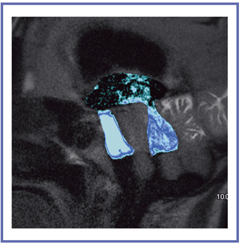

外傷後水頭症では,嚢胞間の髄液の交通はTime-SLIP法で容易に観察できる。図10は,多嚢胞性外傷後水頭症のアキシャル像で,第四脳室内に1個の嚢胞があり,髄液が下方に流れて側壁に当たって跳ね返る様子が描出されている。このような嚢胞内の髄液の流れの描出はTime-SLIP法以外では不可能である。この症例では,各嚢胞間に交通があるという情報がTime-SLIP法によって術前にわかり,V-Pシャントのみで治療を行うという治療法の選択が可能となった。